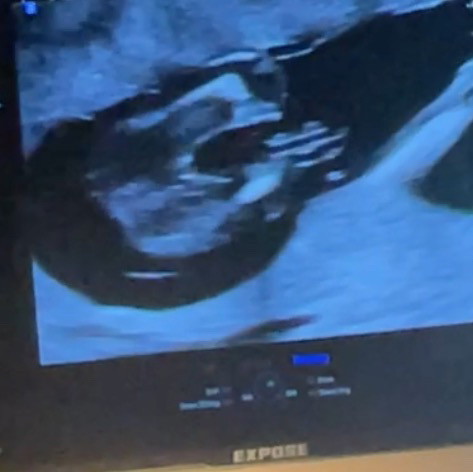

16 วีคคคคคค

แม่ๆช่วยดูหน่อยค่ะน้องเป็น ญ หรือ ช ซาวตอน16วีคค่ะ🥹

น่าจะผู้ ญ นะคะ ของบ้านนี้น้องก็เป็นเเบบนี้ คุณหมอบอกผู้ ญ คะ

ผญรึเปล่าแม่ เห็นกลีบๆ

ผู้หญิงค่ะชัดเลย

ผู้หญิงค่ะ

หญิงค่ะ